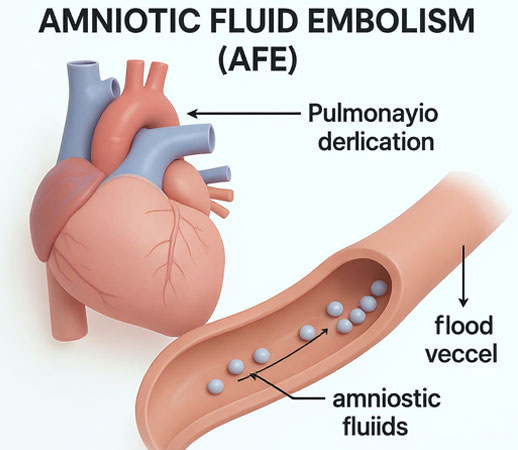

Negligencia Médica